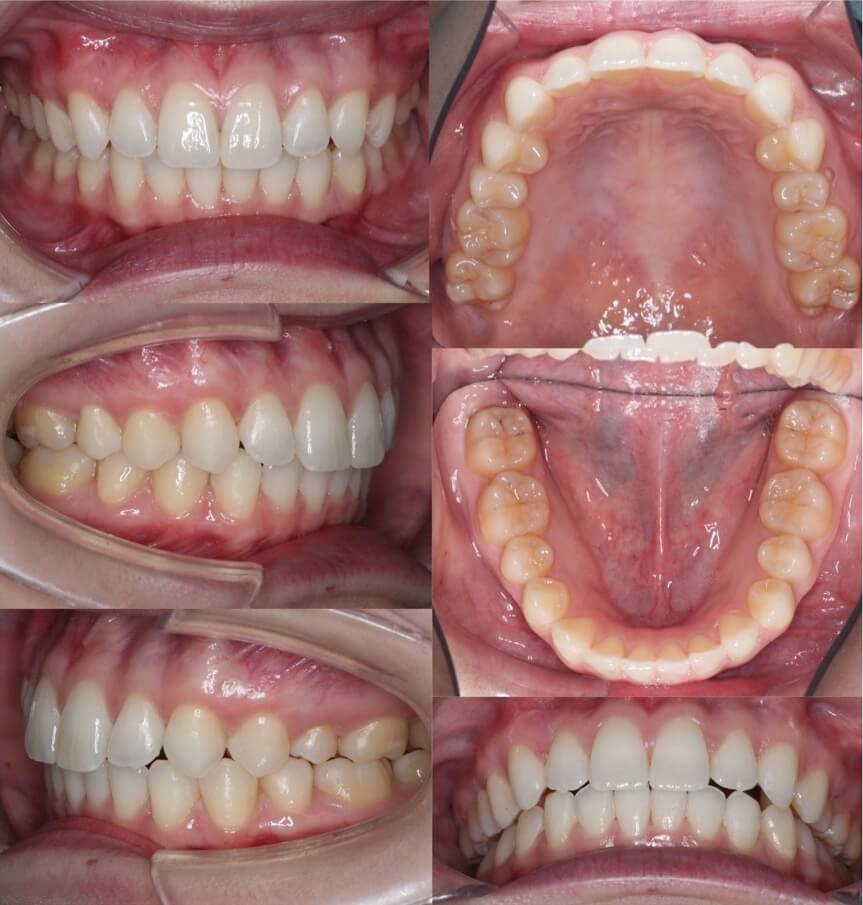

20代女性・唇側矯正装置・2本抜歯

重度の過蓋咬合であったため、唇側ワイヤー矯正装置とアンカースクリューにより、先に上の前歯の圧下(歯茎方向への移動)を行なった後に、ゆっくりと抜歯空隙を閉鎖しました。このように過蓋咬合では前歯に植立するアンカースクリューがあった方が治療が効率的に進みます。

<症例概要>

主訴:前歯の突出と噛み合わせ

年齢・性別:20代女性

住まい:東京都練馬区

症状:過蓋咬合・上顎前突

治療方針:上顎前歯の圧下・抜歯空隙の閉鎖

治療装置:唇側矯正装置

固定装置:歯科矯正用アンカースクリュー(上唇側x2)

抜歯:上左右第一小臼歯(計2本)

治療期間:2年6か月

リテーナー:下フィックスタイプ+上下プレートタイプ

治療費用:968,000(税込)

代表的副作用:痛み・治療後の後戻り・歯根吸収・歯髄壊死・歯肉退縮

▶︎その他の副作用